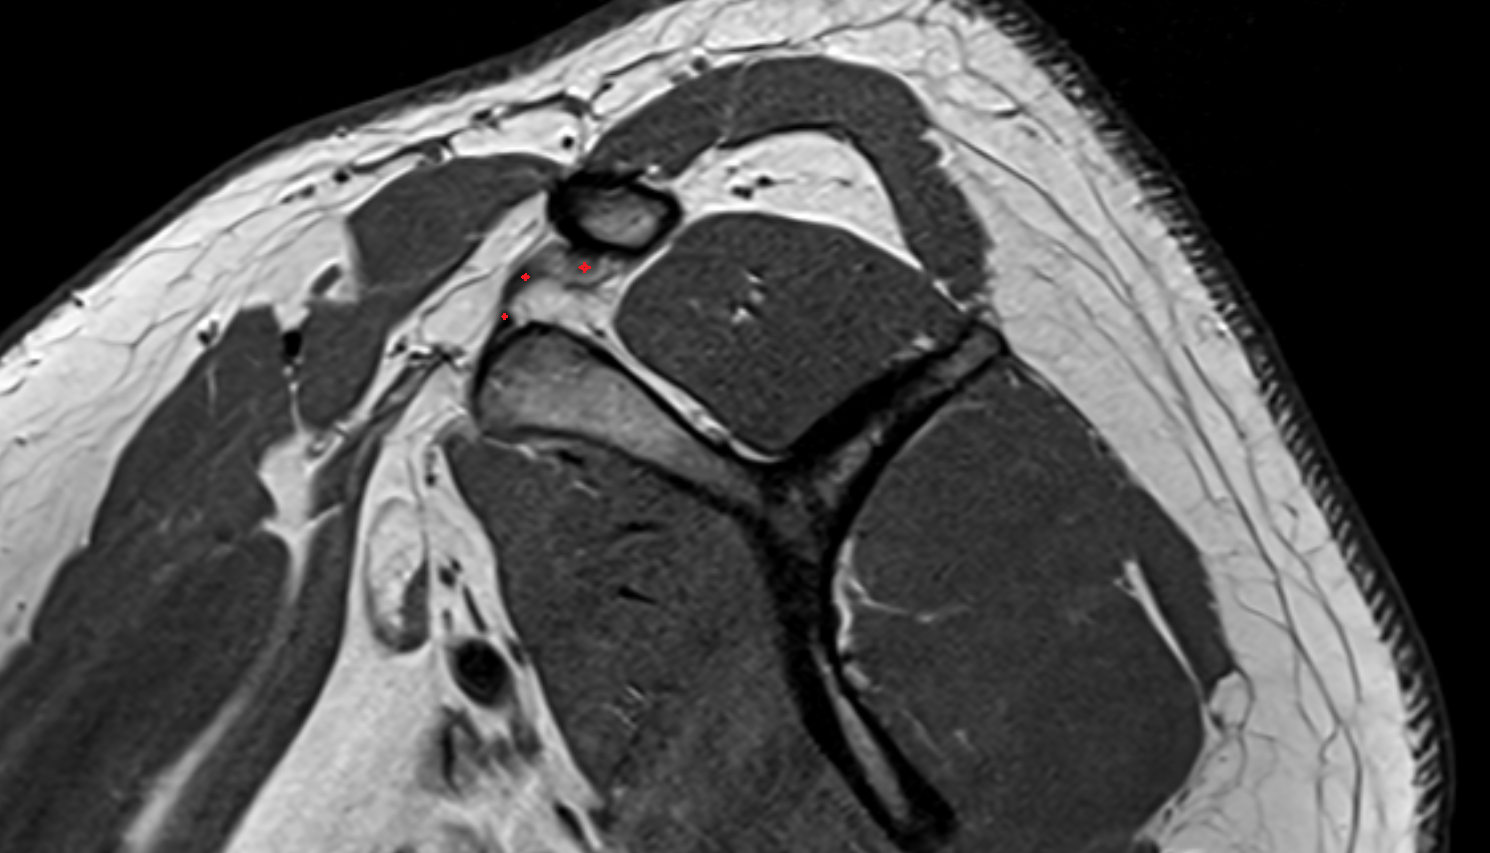

- Subscapularis tendon

- Infraspinatus tendon

- Supraspinatus tendon

- Glenohumeral ligaments

- Shoulder joint (glenohumeral joint)